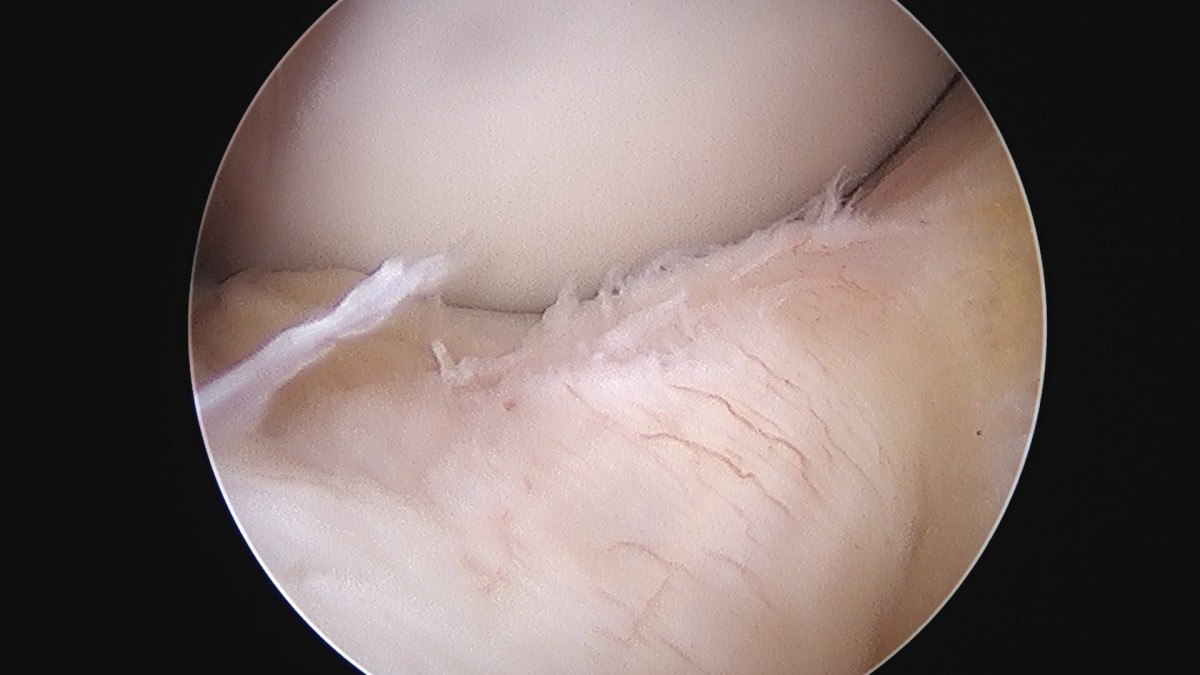

이재상원장님 무릎 반월상 연골판 절제술 김건O 환자

dae765e4d9ac96aee867c9d6292d8784_1758006495_2691.jpg